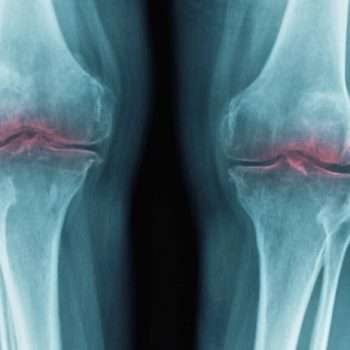

სტენფორდის უნივერსიტეტის მიერ თაგვებზე ჩატარებული კვლევით დადგინდა, ხრტილების დაკარგვა, რომელიც ასაკთან ერთად მოდის, გამოწვეულია ერთი ცილით. აღმოჩენა მიუთითებს მკურნალობის მეთოდებზე, რომლებმაც შეიძლება ერთ მშვენიერ დღეს ხანდაზმულებში აღადგინოს მოძრაობის უნარი და